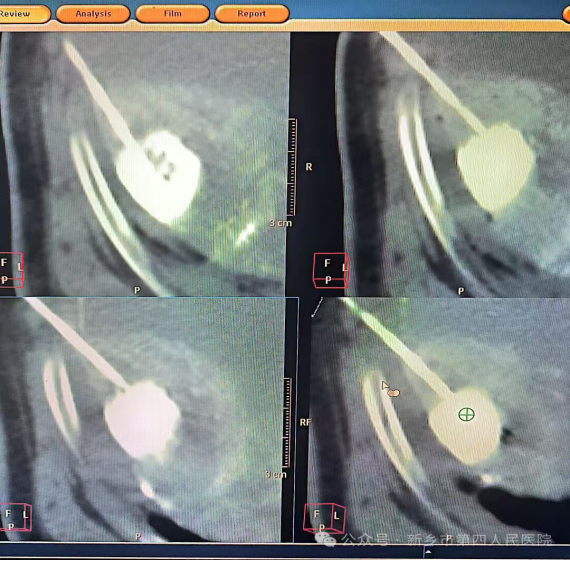

1. 精准定位的“狙击手”模式

CT影像能够提供毫米级的精准定位。尤其是对于深部小病灶(如早期肺部小结节),CT引导可以帮助医生一次性准确到达,避免“盲穿”多次尝试的风险。

案例小故事:张先生肺部发现一个仅8毫米的小结节,传统方法很难精准穿刺。在CT引导下,医生像使用高倍望远镜一样,清晰看到穿刺针一步步接近目标,一次成功完成活检。